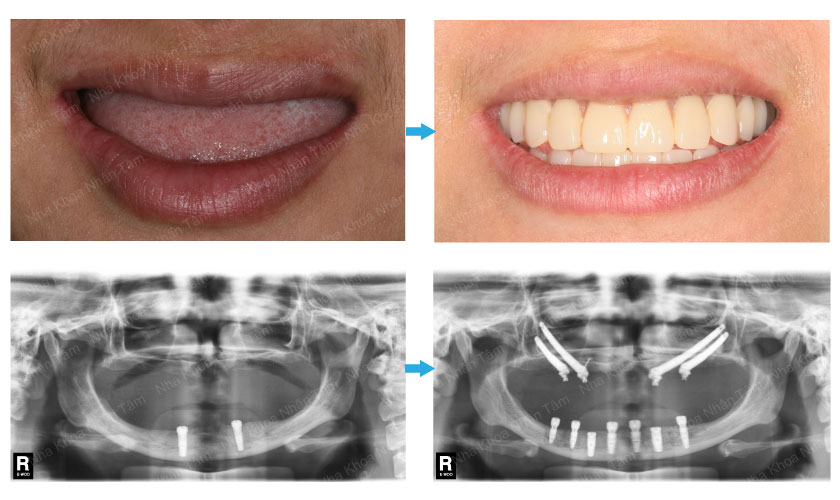

Trồng răng sứ là một trong những phương pháp phục hồi răng thẩm mỹ bằng việc sử dụng một răng sứ nhân tạo để thay thế một răng đã mất. Đã có khá nhiều người biết đến dịch vụ này, xong không phải ai cũng có thể biết được cụ thể trồng răng sứ bao nhiêu.